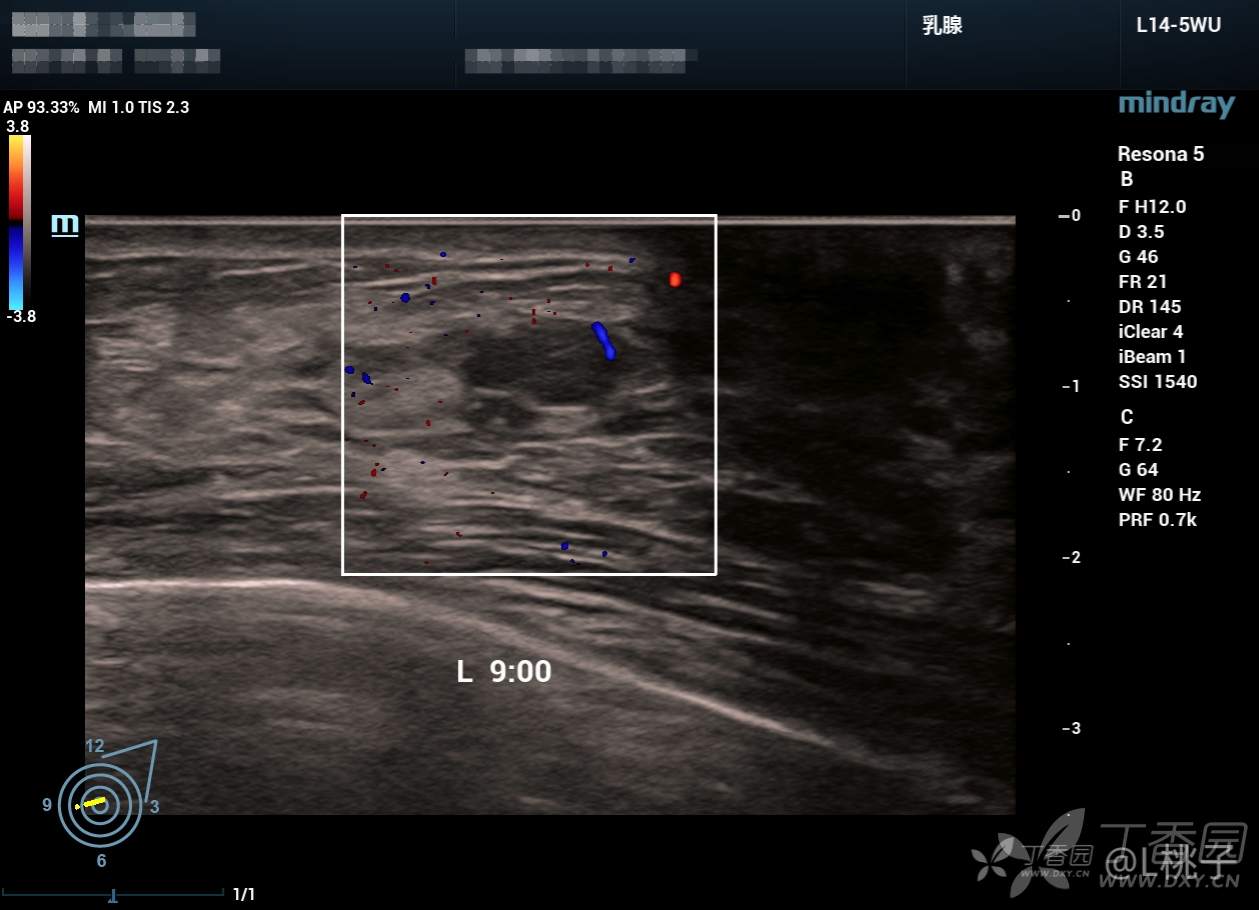

发部分乳腺结节的病例

大家考虑一下分级

病例1: